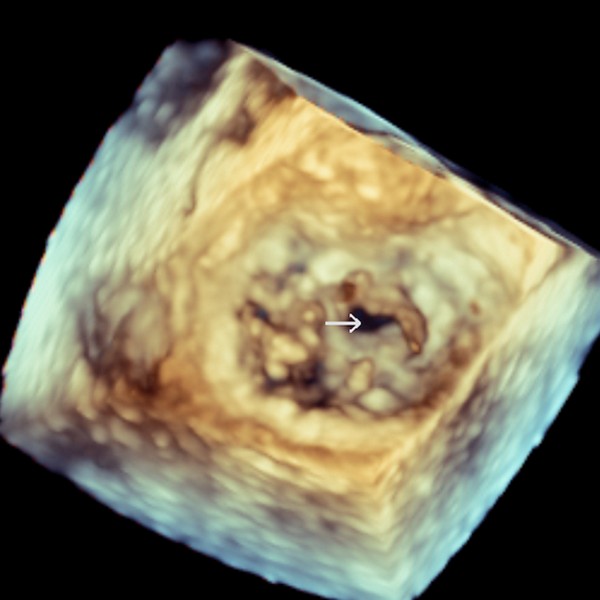

▲僧帽瓣前葉穿孔。

若只是單純的二尖瓣逆流是有機會靠微創手術治療的,但蔡先生的病況並不單純,因為他的二尖瓣不但逆流,還有一個1公分左右的大破損,周圍更出現許多細菌感染增生的贅生物,使得抗生素藥物治療效果有限。考量病人的情況若使用微創術式相當耗時,且有生命危險,醫療團隊決定以傳統手術方式治療。先在病人胸前正中處切一20公分的切口,鋸開胸骨後,將心臟麻痺停跳,找到二尖瓣後予以切除並清除周圍的贅生物,最後植入新的人工瓣膜並縫合左心房,在心臟復跳後縫合傷口。術後兩天,病人肺水腫大幅改善,持續以抗生素治療六個禮拜後,蔡先生康復出院。